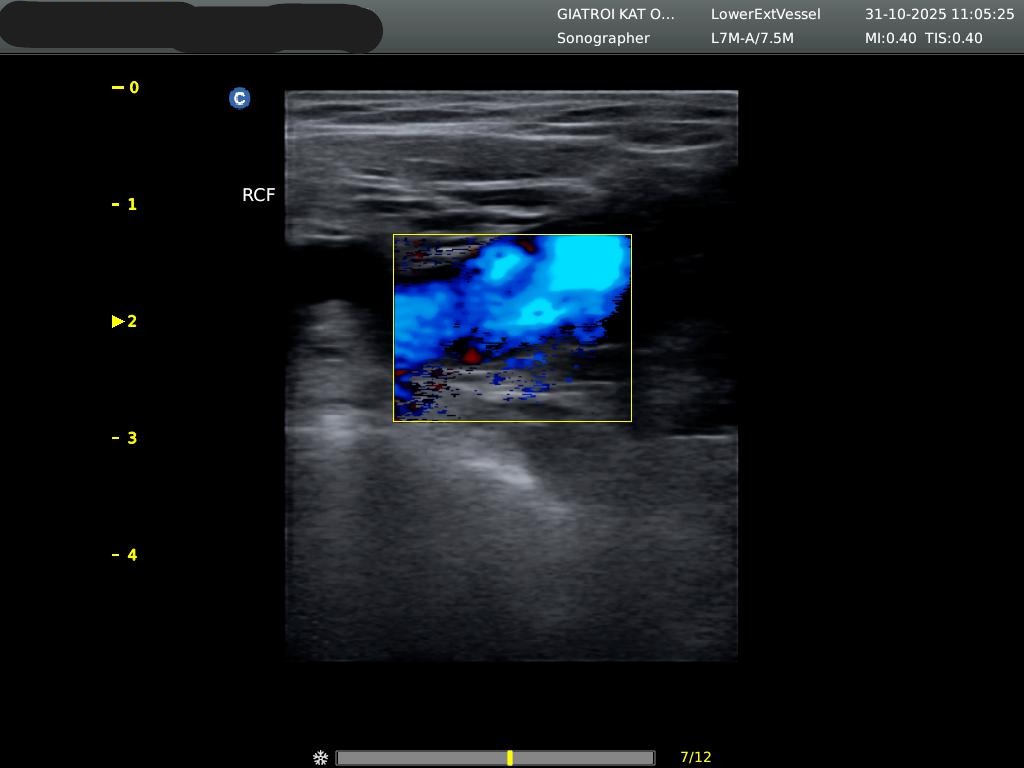

Τι είναι το triplex αγγείων και πότε χρειάζεται;

Το triplex είναι υπερηχογράφημα που απεικονίζει τη ροή του αίματος σε φλέβες και αρτηρίες. Χρησιμοποιείται για τον έλεγχο θρόμβωσης, στενώσεων, αποφράξεων ή ανευρυσμάτων σε άνω και κάτω άκρα, καρωτίδες και κοιλιακή αορτή.